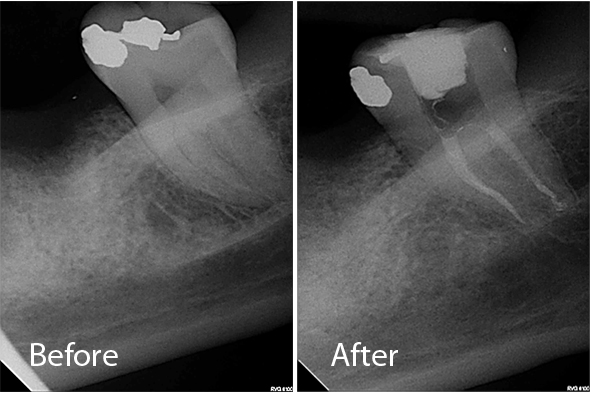

These X-ray images demonstrate the quality and precision of Dr. Portugeys' endodontic procedures. Click any image to view it larger.

Retreatment Molar / Post Removal